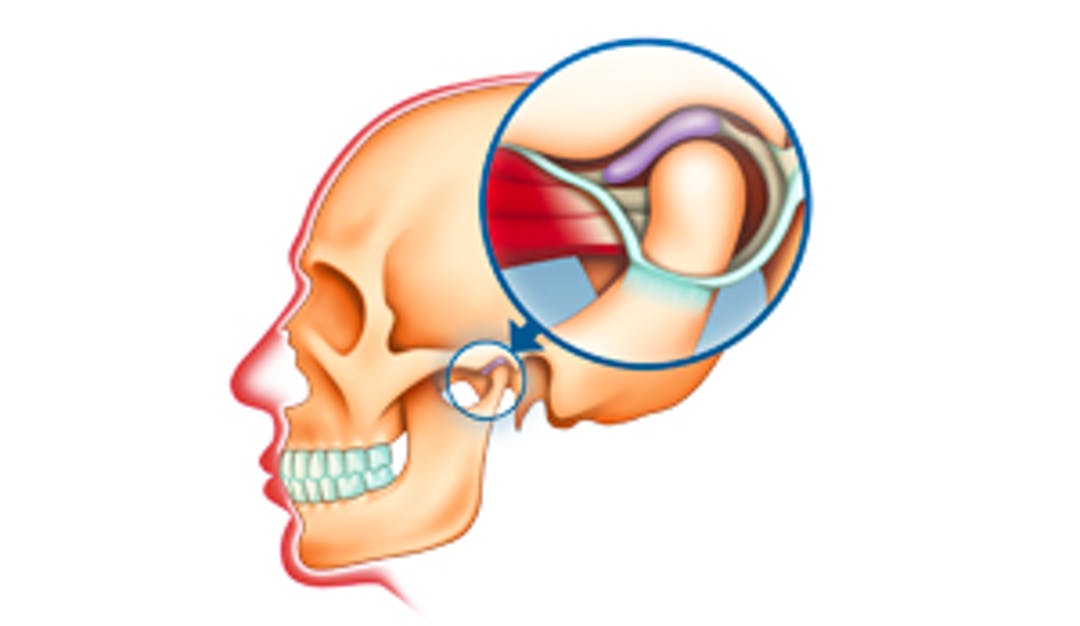

Langvarig og kraftig gaping kan noen ganger gi forskyving av en liten bruskskive som ligger inne i leddet. Dette kan medføre klikking ved gaping. Over tid kan dette resultere i låsing av kjeven og redusert gapehøyde.